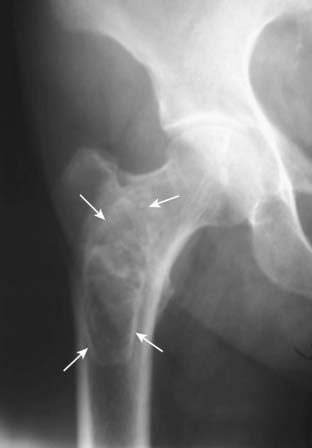

Figure 21-9 Avascular necrosis of the left femoral head in a patient on long-term steroids for lupus erythematosus.

A close-up view of the left femoral head shows a zone of increased sclerosis in the superior aspect of the femoral head (solid white arrows), a characteristic finding of avascular necrosis of the head. The linear, subcortical lucency (solid black arrow) represents subchondral fractures seen with this disease, called the crescent sign. Notice that the disease is isolated to the femoral head and involves neither the joint space nor the acetabulum, i.e., this it is not an arthritis.